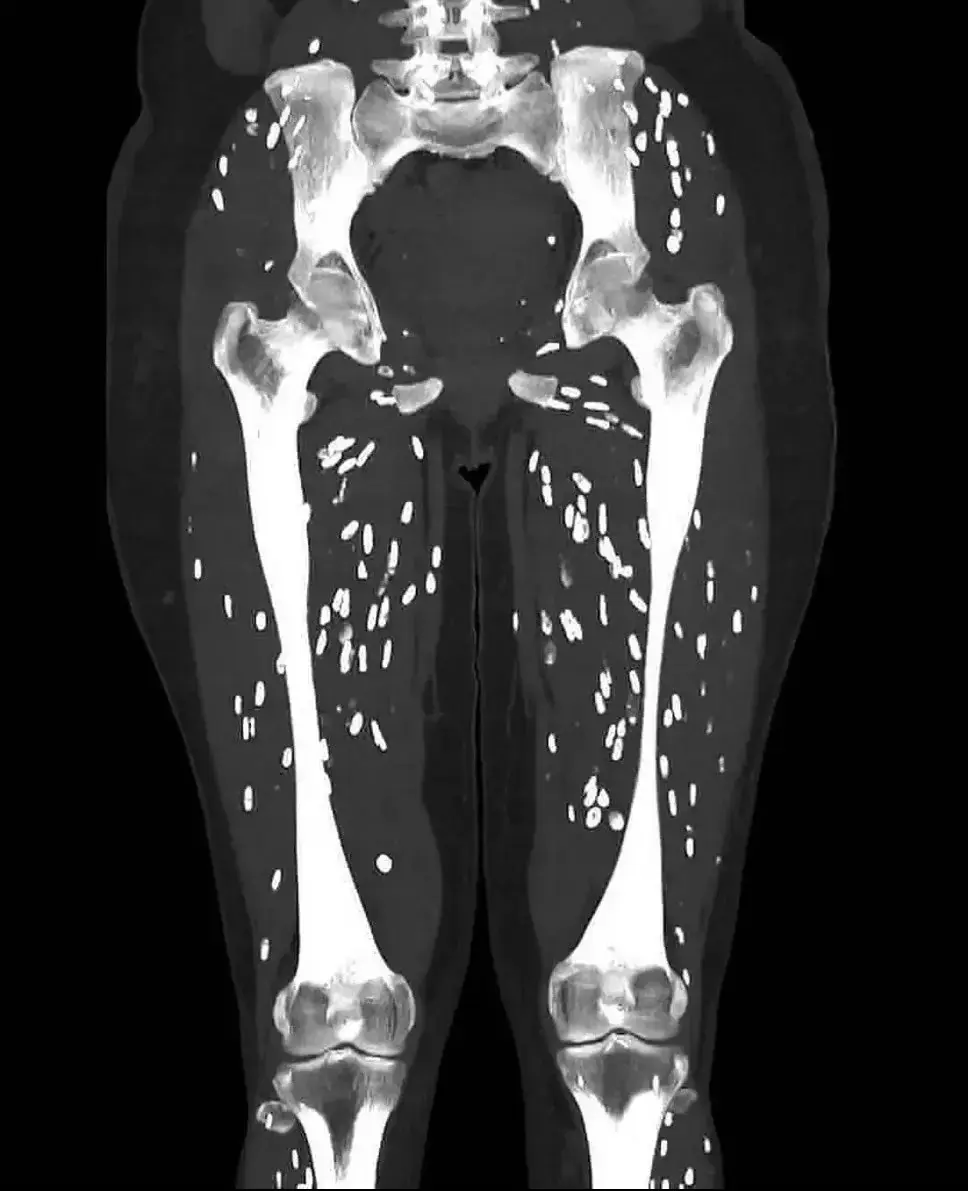

Doctor shares horrifying scan showing patient's legs after eating undercooked pork

A doctor has taken to social media to share a concerning scan photo of a woman's legs, before asking his followers what they thought the diagnosis could be.

Describing the image as "one of the craziest CT scans he's ever seen", Sam Ghali, M.D. - who boasts more than 630,000 followers on X - shared the image of a female patient's legs.

However, white blotches could be seen all over the scan image, leading to concerns from followers.

After giving people 24 hours to guess what they thought the answer could be, Dr. Ghali revealed that the patient in question had been suffering from Cysticercosis, which he explained is the "infamous parasitic infection caused by ingestion of larval cysts of Taenia Solium, also known as: Pork Tapeworm".

The scan in the tweet shows the body's natural inflammatory response to the cysticerci - which kills them off and causes calcification, known as "rice grain calcifications" due to their appearance.